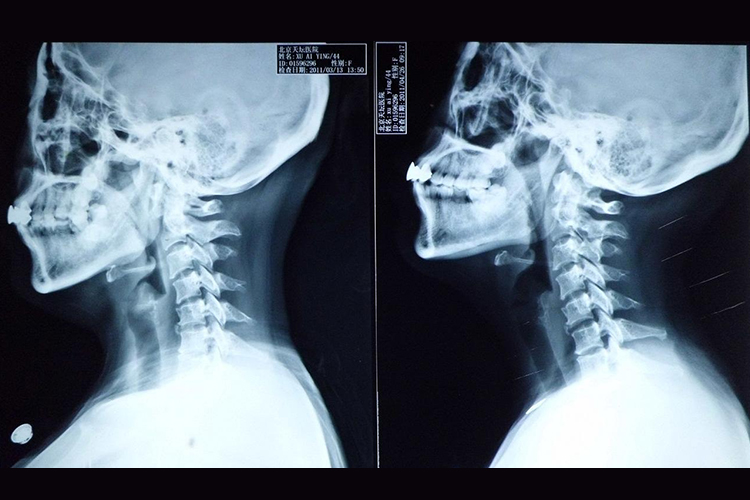

健康的颈椎椎体较小,活动度较大,横断面呈椭圆形,上、下关节突的关节面呈水平位。

健康的颈椎共由7块椎骨组成,颈椎椎体较小,横断面呈椭圆形,上下关节突的关节面呈水平位。第3-7颈椎体上面侧缘向上突起称椎体钩。椎体钩与上位椎体的下面两侧唇缘相接,则形成钩椎关节。

颈椎椎孔较大,呈三角形。横突有孔称横突孔,有椎动脉和椎静脉通过。椎体前面弧状隆起,上下缘附着前纵韧带,后缘较平坦,有滋养血管出入孔,上下缘有后纵韧带附着。第2-6颈椎的棘突较短,末端分叉。